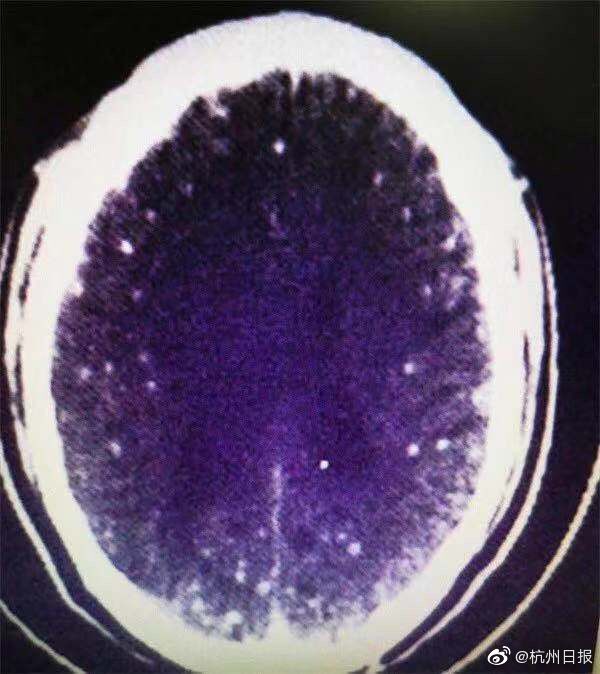

浙江46岁男子吃了顿火锅后,脑子里长满寄生虫!都是因为涮了这个吃

朱大哥是浙江衢州人,今年在武汉工作。一个月前,朱大哥在菜市场买了些猪肉、羊肉,自制了一顿麻辣火锅吃。后来,朱大哥白天时常觉得头晕、头顶胀痛,半夜多次出现肢体抽搐、口吐白沫等癫痫症状。他回浙江后到浙一医院求诊,最后被诊断为脑囊虫病。医师解释说猪肉、羊肉可能本身有猪囊尾蚴虫寄生,肉没有涮熟透,导致虫通过消化道进入了脑子。经过住院行驱虫、降颅压治疗后,目前朱大哥已恢复了。医生提醒,多种脑寄生虫病都是病从口入,关键是改变不良的饮食习惯。(记者 柯静)